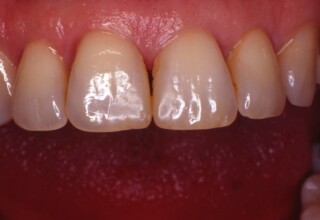

Δύσχρωμα απονευρωμένα δόντια

Μια ιδιαίτερη περίπτωση δύσχρωμων απονευρωμένων δοντιών που ο κεντρικός είχε βλάβη από εξωτερική απορρόφηση. Έγινε καθαρισμός του κεντρικού από την βλάβη και επειδή δεν μπορούσε να λευκανθεί λόγω της επαφής με τα ούλα, σφραγίστηκε σε πρώτη φάση, μετά λευκάνθηκε και στο τέλος έγινε η τελική αποκατάσταση.